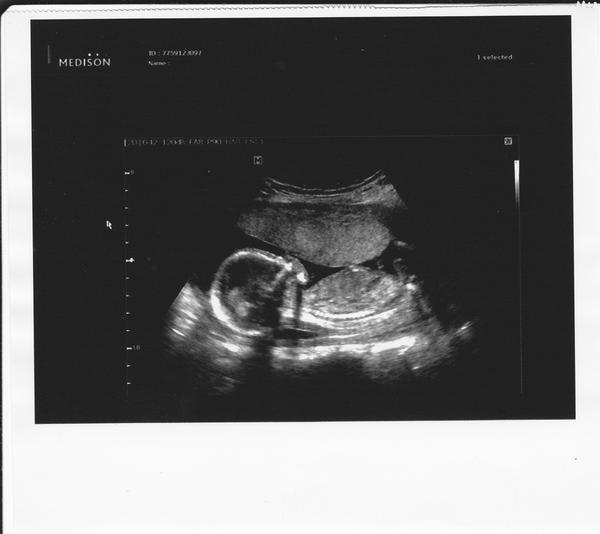

@lovebaby jo, jo už začínají první pohyby ... nepravidelně ... nakonec to vypadá, že se celá rodina bude řídít mým přáním, nechat se překvapit 😎 , jenomže pan doktor má úplně nový ultrazvuk, takže už jsem miminko viděla ze všech stran ... 😎 😉 i v 4D 😲